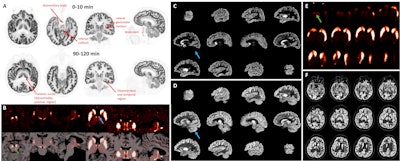

F-18 SynVesT-1 images at early (0-10) and late (90-120 minute) times postinjection. There is clear identification of high flow regions in the early images. The late images show the synaptic (SV2A) pattern which differs from the flow pattern, e.g., in the thalamus. B. 11C-PHNO binding potential (BPND) images shown in transverse, coronal, and sagittal orientations of PET alone and PET overlaid with MRI. Left: Region of substantia nigra (green arrow, max display: 4.0). Right: Thalamic region (max: 2.5) showing focal bilateral binding in a specific thalamic nucleus (blue arrow, likely anteroventral nucleus). C. Sagittal images of 11C-LSN3172176 M1 muscarinic cholinergic BPND (max display: 10). D. R1 images of the same tracer (max: 2). Cerebellum (blue arrow) shows no specific binding (C) and high tracer delivery (D). E. 18F-FE-PE2I dopamine transporter BPND images (zoomed, max display: 6) showing striatum and substantia nigra (green arrow). F. R1 images of the same tracer (max: 2) with inset showing zoomed region in E.Image courtesy of Richard Carson, PhD

In the study, Carson and colleagues conducted human brain imaging with both the NeuroEXPLORER and the latest HRRT system. Multiple PET radiotracers were administered to observe synaptic density, dopamine receptors and transporters, muscarinic cholinergic receptors, and glutamate receptors. Images from both scanners were then compared.

A striking improvement in image contrast and quality of the NeuroEXPLORER compared to the HRRT was evident, according to the findings. The NeuroEXPLORER images demonstrated low noise and exquisite resolution, showing focal uptake in specific brain nuclei.